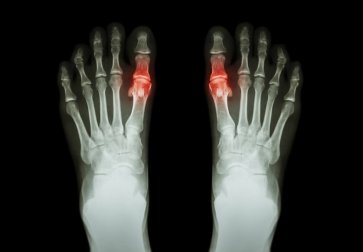

Une crise de goutte est une affection caractérisée par des douleurs intenses, un gonflement et des rougeurs survenant au niveau de certaines articulations comme le poignet, la cheville ou le genou. Cependant, le plus souvent, elle se produit au niveau du gros orteil.

La crise de goutte apparaît de façon très brutale et est très douloureuse. L’articulation touchée est gonflée et rouge.

- Au départ, seules une ou plusieurs articulations sont touchées. Ce sont généralement celles du gros orteil, du genou ou de la cheville.

- L’articulation atteinte est chaude et rouge. Une inflammation se déclenche et est généralement molle et gonflée.